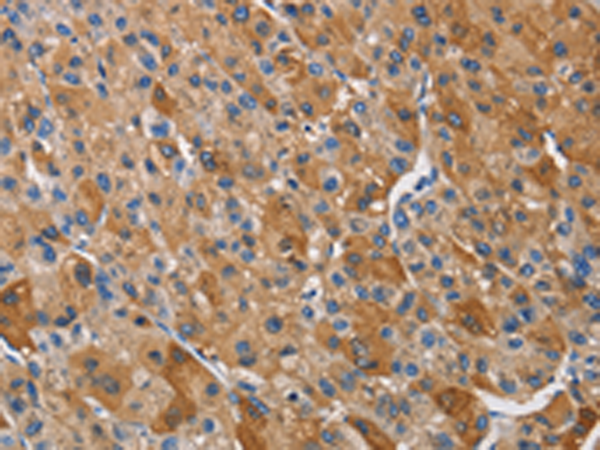

分类: 科研抗体货号: P07408别名: hK1; KLKR; Klk6应用: IHC反应种属: Human